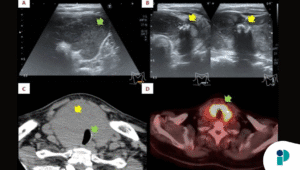

Un grupo de especialistas ha documentado un caso clínico inusual que pone a prueba los protocolos estándar de diagnóstico oncológico: el hallazgo de un Tumor Fibroso Solitario (TFS) localizado en